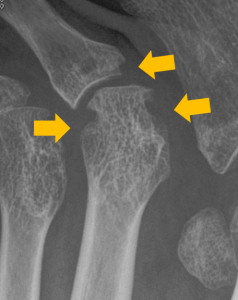

人間の耳には聞こえない周波数の音波(超音波)を体内に照射して、その反射を測定することで体内の構造を画像化する検査です。妊婦健診で赤ちゃんの姿を見るのに使われる検査と同じですが、関節リウマチでは主に関節や腱の周囲の腫れ(滑膜炎)を見るのに使います。

以前は診察の際に手で触って「腫れているか」「押したら痛いか」ということでしか推定できなかった関節の炎症が、エコー検査を行うことで診察室でも直接画像化して確認することができるようになりました。検査も安価で、身体への害もほぼ無いため、関節リウマチ診療で急速に普及しました。痛みを感じた際に「それがリウマチの炎症によるものかどうか」を簡易的に判別する方法として外来で使用されています。

画像:エコー検査で確認できる滑膜炎の血流

エコー検査で確認できる滑膜炎の血流